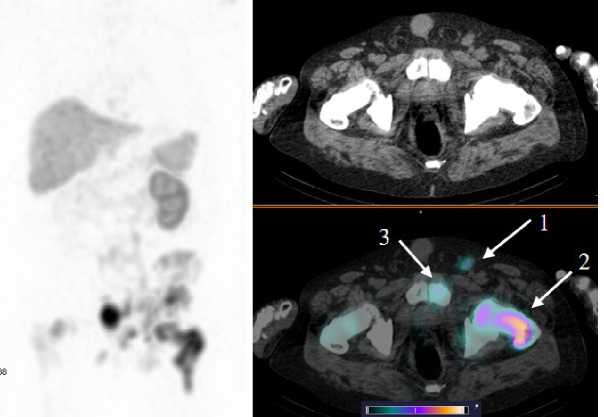

У 4 пациентов, вошедших в исследование, по данным референсных методов исследования, было выявлено метастатическое поражение костных структур, у 2 пациентов — поражение ЛУ. Накопление [99mTc]Tc-HYNIC-PSMA в патологических участках отмечалось у 3 больных с костными метастазами (SUVmax по всем костным очагам 28,57 ± 16,09) и у одного пациента с поражением ЛУ (SUVmax 15,32 ± 8,11). Примеры накопления [99mTc]Tc-HYNIC-PSMA в ПСМА-позитивных костных и лимфогенных метастазах представлены на рис. 4, 5.

Рис. 5. MIP-реконструкция, КТ и совмещенное ОФЭКТ/КТ изображение больного раком предстательной железы с множественными метастазами в кости и лимфатические узлы малого таза через 2 ч после инъекции [99mTc]Tc-HYNIC-PSMA. На ОФЭКТ-КТ изображении стрелкой отмечено накопление РФЛП в паховом лимфатическом узле слева (1) SUVmax 22; бедренной кости слева (2) SUVmax 53; лонной кости слева (3) SUVmax 22,8

Fig. 5. MIP reconstruction, CT and SPECT/CT image of a patient with prostate cancer with multiple metastases to bones and pelvic lymph nodes 2 hours after injection of [99mTc]Tc-HYNIC-PSMA. Аccumulation of radiopharmaceutical in the pathological areas is indicated by the arrow on the SPECT-CT image: inguinal lymph node on the left (1) SUVmax 22; femur on the left (2) SUVmax 53; pubic bone on the left (3) SUVmax 22.8